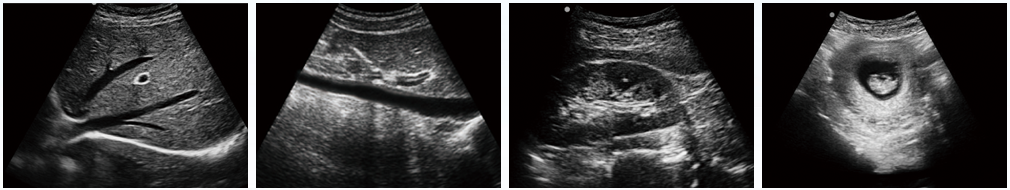

設(shè)備用途說明:主要應(yīng)用于腹部、淺表組織、生殖系統(tǒng)、泌尿系統(tǒng)等器官的檢查

全數(shù)字成像技術(shù),真實(shí)、細(xì)膩地顯示組織結(jié)構(gòu);